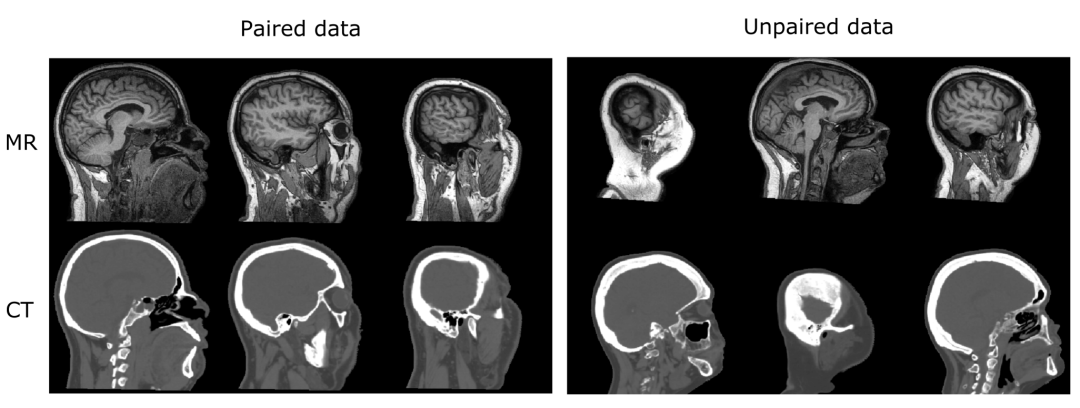

3 无条件监督数据仿真GAN

在有些场景中我们需要成对的不同类型的图像,比如在放射治疗中的MRI与CT,但是高质量成对数据获取难度高,图像翻译框架CycleGAN是一个不依赖于成对数据集的框架,可被用于从某一个域的数据转换为另一个域的数据。

[6] Wolterink J M, Dinkla A M, Savenije M H F, et al. Deep MR to CT synthesis using unpaired data[C]//International workshop on simulation and synthesis in medical imaging. Springer, Cham, 2017: 14-23.

[7] Chartsias A, Joyce T, Dharmakumar R, et al. Adversarial image synthesis for unpaired multi-modal cardiac data[C]//International workshop on simulation and synthesis in medical imaging. Springer, Cham, 2017: 3-13.